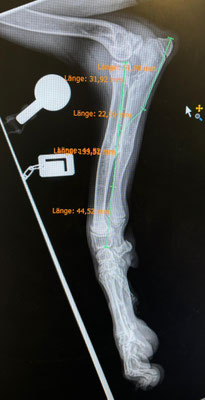

Im September 2025 haben wir Ihnen die kleine Finija vorgestellt: Gerade einmal vier Monate alt, wurde sie in einem erschütternden Zustand gefunden. Beide Hinterbeine waren gebrochen, eine Fortbewegung war für sie nur noch auf den Vorderpfoten möglich. Trotz starker Schmerzen zeigte Finija eine unglaubliche Willenskraft – ein kurzes Video aus…